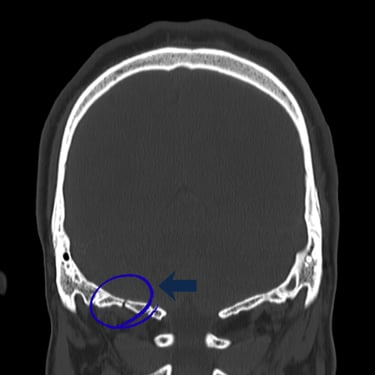

El trauma craneal severo es una de las principales emergencias neurológicas y puede poner en riesgo la vida del paciente. El diagnóstico por imágenes, a través de tomografía computarizada o resonancia magnética, es fundamental para identificar hemorragias, fracturas o lesiones cerebrales y definir el tratamiento adecuado. La evaluación temprana y la intervención oportuna por parte del neurocirujano permiten reducir complicaciones y mejorar el pronóstico neurológico. Una atención especializada y multidisciplinaria resulta esencial para garantizar la recuperación y preservar las funciones cerebrales.